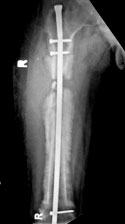

Fractures

• Acute Fracture

- Nailing